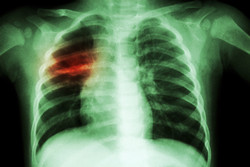

Diagnosi rapide, precise e convenienti per combattere le infezioni respiratorie

Le linee guida per la cura dei pazienti affetti sia da HIV che da tubercolosi (TB) andrebbero aggiornate, è quanto afferma un nuovo studio in parte finanziato dal progetto dell’UE RID-RTI.

Recentemente pubblicato sugli Annals of Internal Medicine, lo studio ha scoperto che iniziare la terapia per l’HIV entro due settimane dalla diagnosi della TB può migliorare il tasso di sopravvivenza nei pazienti affetti da entrambe le infezioni con un numero molto ridotto di immunociti. Per chi ha un sistema immunitario forte, però, sembrerebbe meglio aspettare fino alla fine dei sei mesi di terapia per la TB prima di iniziare la terapia per l’HIV. Lo studio raccomanda di aggiornare le linee guida tenendo conto di queste scoperte. Curare HIV e TB simultaneamente si è rivelato difficile per una serie di ragioni, come per esempio l’esigenza che i pazienti prendano diverse pillole e le interazioni tra un farmaco e l’altro oltre al sovrapporsi di effetti collaterali. Questo studio in particolare si proponeva di esaminare le tempistiche ottimali per iniziare la terapia per l’HIV alla luce dei recenti esperimenti clinici. È un esempio di come il progetto RID-RTI, che ha avuto inizio a luglio 2012, abbia contribuito a migliorare le probabilità di sopravvivenza di pazienti con infezioni del tratto respiratorio. Queste infezioni sono causate da una serie di patogeni batterici, virali e fungini e sono tra le cause principali di morbilità e mortalità negli adulti e nei bambini in tutto il mondo. Le infezioni del tratto respiratorio come TB e polmonite sono un problema sanitario mondiale. Nel 2013 ci sono stati, secondo le stime, 9 milioni di nuovi casi di TB, con tra 1,3 e 1,5 milioni di morti. Più persone contraggono la TB nei paesi in via di sviluppo a causa di un sistema immunitario debole dovuto in gran parte al numero elevato di infezioni da HIV e allo sviluppo dell’AIDS. Secondo l’Organizzazione mondiale della sanità (OMS), la polmonite è la causa principale di morte nei bambini a livello mondiale e uccide secondo le stime ogni anno 1,4 milioni di bambini al di sotto dei cinque anni di età. Una delle ragioni per cui le infezioni del tratto respiratorio continuano a proliferare è che è molto difficile diagnosticarle velocemente e accuratamente. I test a attualmente disposizione richiedono molto tempo e di conseguenza, i pazienti che presentano sintomi di un’infezione del tratto respiratorio spesso sono curati in modo uniforme con antibiotici, senza identificare con precisione il microorganismo causa dell’infezione. Questo può portare a un uso improprio degli antibiotici, che a sua volta aumenta la morbilità e la mortalità del paziente. Per risolvere questo problema, il progetto RID-RTI – costruito intorno a un consorzio di PMI, università e ospedali in Finlandia, Francia, Irlanda e Regno Unito – ha cercato di sviluppare un test diagnostico molecolare rapido in grado di identificare un’ampia gamma di microorganismi responsabili delle infezioni del tratto respiratorio. Questo porterà a cure più adeguate applicate sin dalla prima consultazione. Il test, che è costruito su una semplice piattaforma diagnostica in cui si inserisce il campione per ottenere un responso, sarà conveniente e facile da usare e sarà in grado di fornire i risultati in meno di due ore. Questo lo distingue dalle attuali tecnologie diagnostiche. Si spera che la velocità e la precisione della piattaforma rivoluzionino il modo in cui vengono curate le infezioni del tratto respiratorio. Inoltre attualmente si sta sviluppando un piano di applicazione per assicurare che i risultati del progetto possano essere tradotti in prodotti commerciali. Il fine ultimo sono prodotti convenienti e facili da usare da impiegare nella routine degli ospedali. Il progetto RID-RTI si concluderà alla fine di dicembre 2015. Per ulteriori informazioni, visitare: RID-RTI https://www.rid-rti.eu/rid-rti/home_page(si apre in una nuova finestra)